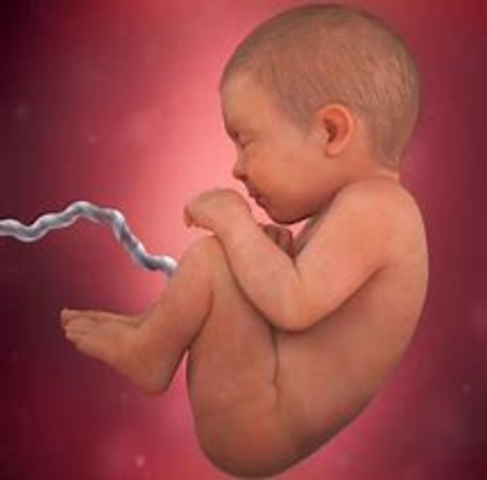

Imagen prenatal 1

Período de transición entre la formación del embrión (embriogénesis) y la de los órganos (organogénesis) del futuro bebé. Los primeros latidos cardíacos se manifiestan hacia el 23.º día. El embrión adquiere su forma definitiva:El embrión flota en medio de la cavidad amniótica, unido a la parte externa del huevo por el cordón umbilical, que se está formando. Al final de este primer mes, el embrión mide 5 mm.